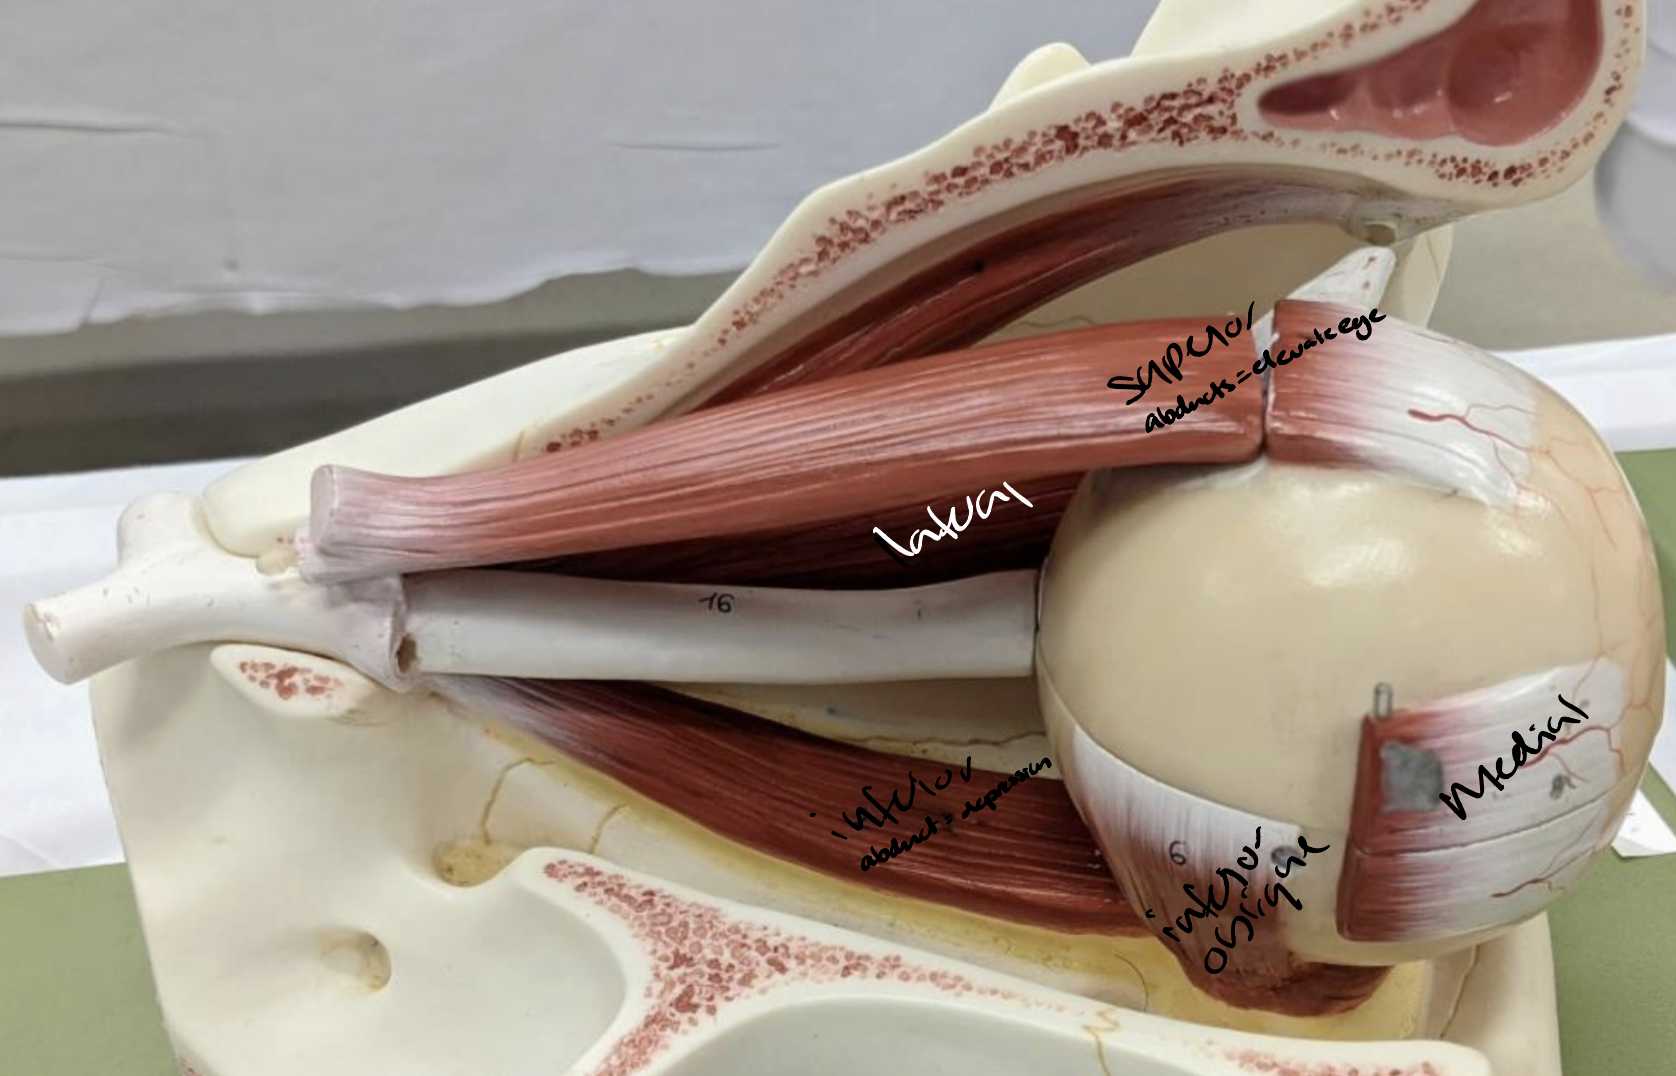

Eye Muscles

Fibrous tunica: sclera and cornea • Vascular tunica or uvea: iris

Pupil

Superior rectus

Medial rectus

Lateral rectus

Inferior rectus

Inferior oblique

Superior oblique

Optic nerve